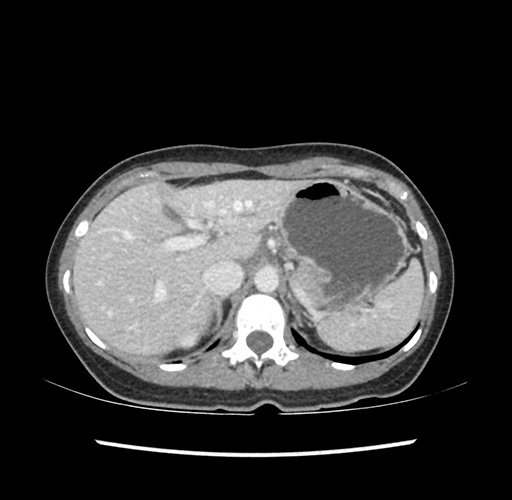

Imaging Analysis

Look through the patient's CT scan to identify any areas of concern for the necessary procedure.

Based on your CT findings, which issue(s) would give reason for "planned slowing down moment(s)" in this case?

Considering a standard left lateral sectionectomy procedure, what step(s) of the operation would you do differently in this case ?